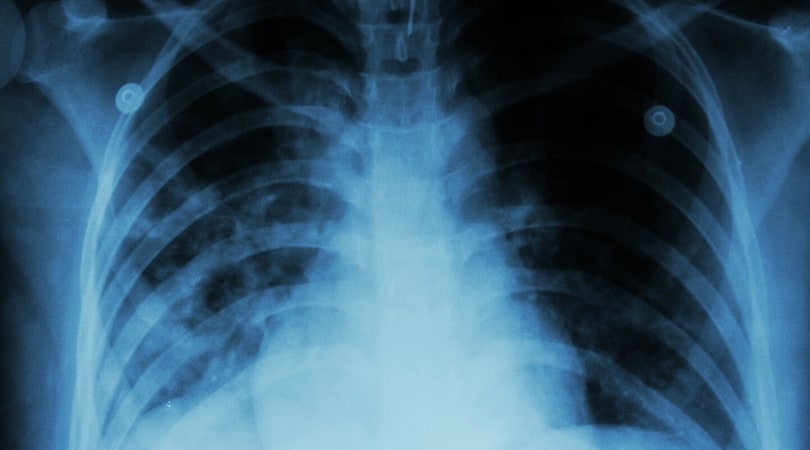

Туберкулез представляет собой инфекцию бактериального типа. Возбудителями болезни являются микобактерии из семейства Mycobacterium tuberculosis complex. Болезнь чрезвычайно заразна и передается воздушно-капельным путем. В большинстве случаев туберкулез поражает легкие, однако встречаются костные и церебральные типы данного заболевания, а также болезнь печени, почек или лимфатических узлов.

Помочь определить туберкулез может флюорография. Однако, ввиду того, что при ВИЧ может держаться температура 38-39 градусов, данный способ может не помочь. Поэтому наиболее приемлемым способом определения данного заболевания при СПИДе по праву можно считать компьютерную томографию.